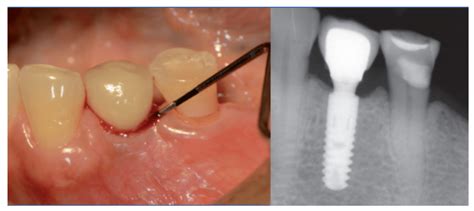

Prevención y tratamiento de las enfermedades periimplantarias | Cátedra UCM-Ticare

La cirugía bucal se completa con una implantoplastia -eliminación de espiras o roscas del implante que han quedado al descubierto por la pérdida de hueso - y pulido de la superficie del implante dental, que ayudará a dificultar en el futuro la acumulación de placa. Para la implantoplastia aplicamos distintos protocolos de fresado con turbina dental o instrumentos de baja velocidad. En algunos casos, a la vez que fresamos, intentamos regenerar el hueso mediante biomateriales o material autólogo.